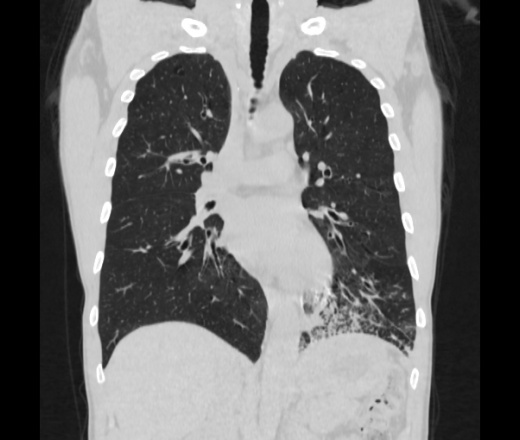

Мужчина пенсионного возраста. Цель назначения КТ ислючение зла в левом легком. Вижу тракционные бронхоэктазы с рубцовой эмфиземой по периферии, скорее всего БЭБ в стадии обострения. Дивертикулы трахеи. Выложил из за того что есть доля сомнения в отношении исключения зно3, немного смущают линии похожие на Керли.

Единственно, не сказал бы, что это тракционные бронхоэктазы, ну, и про линии Керли не вполне понял.

Ну да. Выразился не правильно. На фоне легочного рисунка усиленного линии похожие на септальные, не знаю как называются, при интерстиц.отеке похожие

На мой взгляд, это не главное, указал бы в описании - локально утолщен междольковый интерстиций, и всё